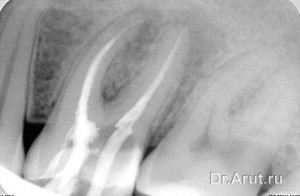

Лечение: трепанация зуба через пломбу, вскрытие полости зуба, ампутация и экстирпация пульпы, инструментальная и медикаментозная обработка корневых каналов. Каналы запломбированы гуттаперчевыми штифтами с AH plus методом вертикальной конденсации. Коронковая часть зуба восстановлена композиционным пломбировочным материалом.

- Пломбирование каналов зуба